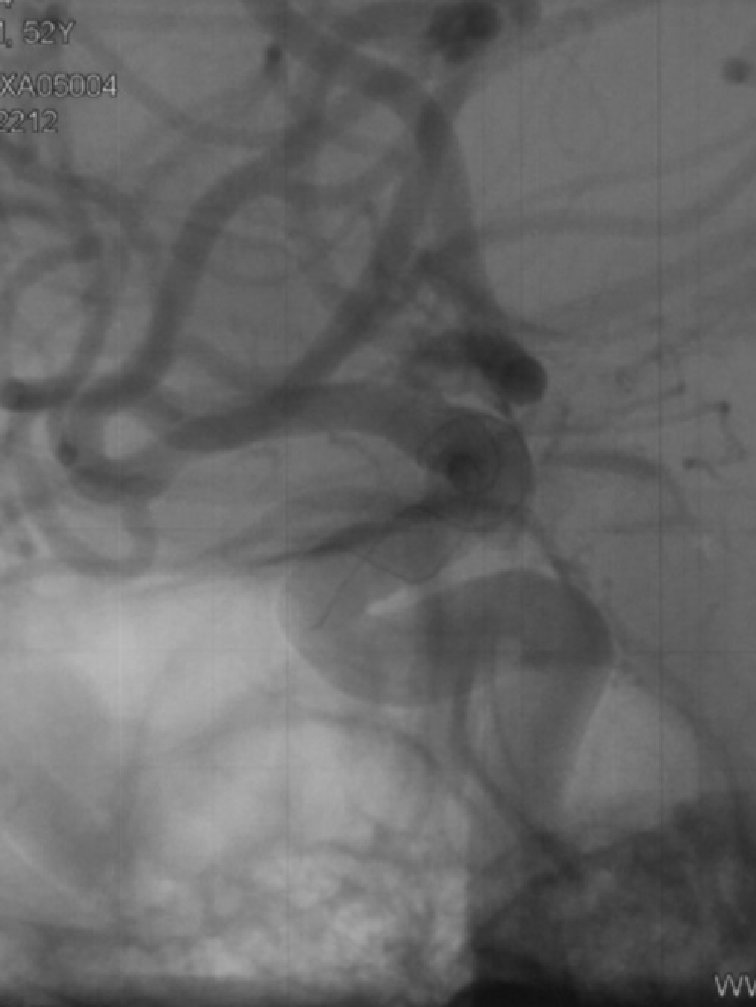

CASE 2

桡动脉释放血流导向装置,椎动脉和锁骨下动脉成角明显;通桥医疗银蛇®DA顺利到达V3段,提供稳定支撑;顺利释放血流导向装置,导管头端无移位。